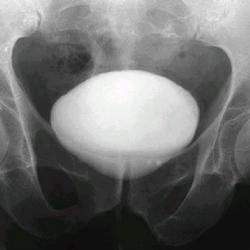

膀胱造影可見膀胱底部有弧形壓跡,或者看到腫物影向上突入,其邊緣常光滑整齊,也可略成為葉狀。後尿道受壓變形,表現為伸長、狹窄和正常曲度增大。此外可見慢性阻塞引起的膀胱改變如錐形膀胱和邊緣不整齊等。

膀胱造影可見膀胱底部有弧形壓跡,或者看到腫物影向上突入,其邊緣常光滑整齊,也可略成為葉狀。後尿道受壓變形,表現為伸長、狹窄和正常曲度增大。此外可見慢性阻塞引起的膀胱改變如錐形膀胱和邊緣不整齊等。如輸尿管或腎區出現放射性影像,是屬反流存在的證據。若輸尿管或腎內有任何明確的放射性增加,即提示膀胱尿有返流。主要用於診斷膀胱瘤、膀胱憩室、外在壓迫,如前列腺肥大等疾病。